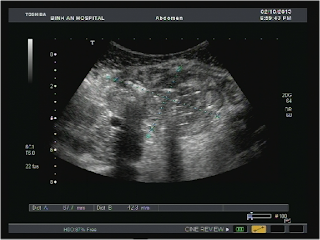

Ultrasound of abdomen detected an abcess in minor pelvis which was thought to be an appendiceal abscess.